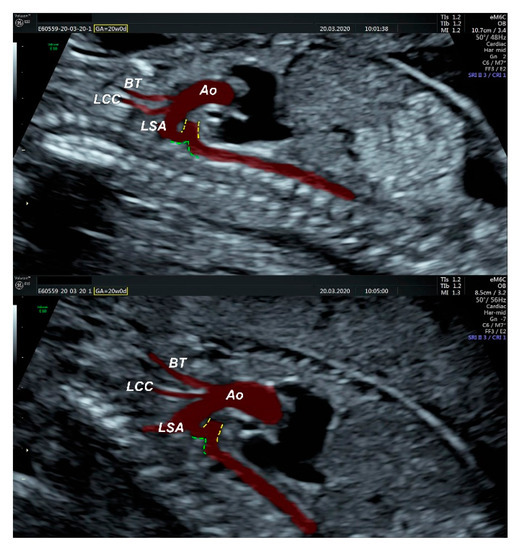

- an isolated aortic arch anomaly (supposedly aneurysmal dilation from which the left common carotid artery emerges) and coarctation of the aorta with the anterograde flow;

- ventricular septal defect, coarctation of the aorta, and a vascular formation located superior from the aortic arch with the appearance of an arteriovenous fistula;

- aneurysmal dilation located above the pulmonary trunk bifurcation and a dilated left common carotid artery with a retrograde flow;

- minor ventricular septal defect with a normal ductus venosus triphasic flow.